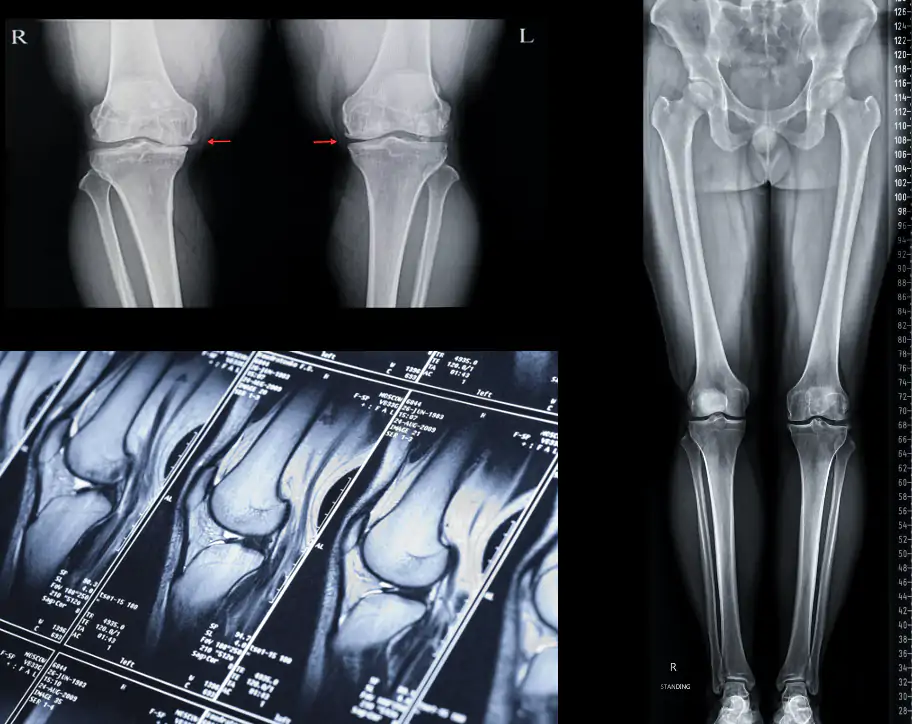

O diagnóstico da artrose de joelho é realizado com uma história clínica e um exame físico adequado. Além disso, o médico ortopedista pode solicitar exames complementares que irão definir melhor a doença e o grau de acometimento da articulação. Os exames mais utilizados para o diagnóstico da osteoartrite de joelho são a radiografia e a ressonância magnética do joelho. Em alguns casos, o joelho pode começar a entortar e uma radiografia panorâmica que mostra os membros inferiores em uma só imagem pode ser necessária para avaliar esse grau de deformidade.

Com os resultados obtidos com os exames complementares, podemos classificar a artrose em leve, moderada ou grave, de acordo com o grau de acometimento articular. A artrose leve é quando ocorre uma pequena destruição da cartilagem, levando a uma leve diminuição no espaço articular. A artrose moderada é quando ocorre uma grande destruição da cartilagem, com uma importante redução do espaço articular. E a artrose grave é quando pode ocorrer deformidades importantes e subluxação articular.